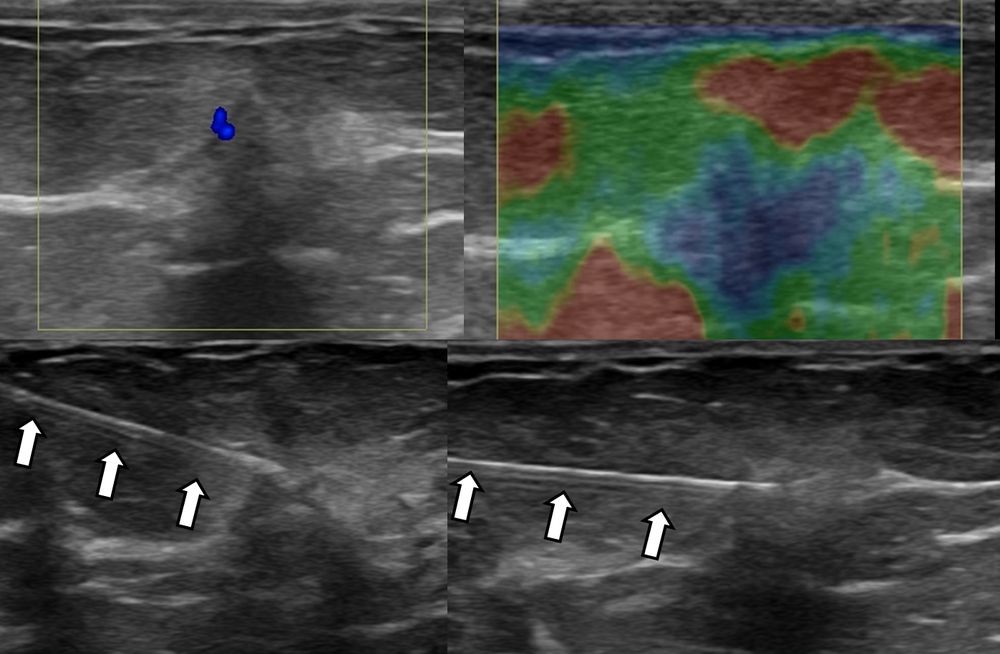

- Υπερηχογραφικά καθοδηγούμενη βιοψία μαστού - core biopsy

Εχει αντικαταστήσει την FNA στις συμπαγείς βλάβες του μαστού, γιατί η ποσότητα του ιστού που συλλέγεται είναι μεγαλύτερη και το αποτέλεσμα πιο αξιόπιστο.